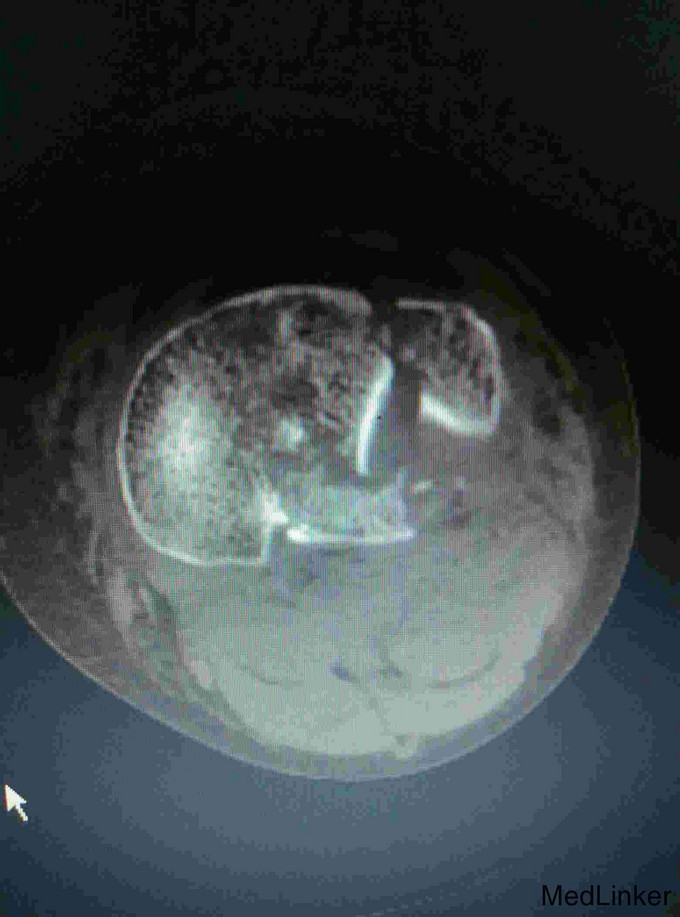

入院查体局部肿胀明显,足背动脉搏动减弱,末梢血运及皮肤感觉减弱,触诊见局部肿胀明显,呈板状,无弹性。入院完善X线片及CT扫描等检查,同时做了下肢彩超提示无血管损伤及栓塞。